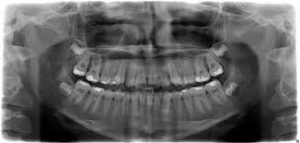

Zdjęcie panoramiczne – zdjęcie wszystkich zębów szczęki i żuchwy przydatne przy ogólnym przeglądzie stanu uzębienia, planowaniu leczenia protetycznego, leczeniu ortodontycznym itp.

2

Zdjęcie panoramiczne szczęki i żuchwy .